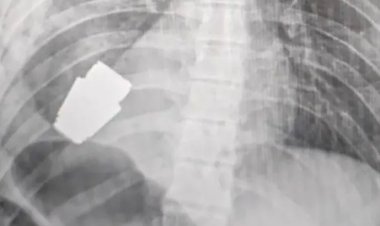

ইউক্রেনীয় সেনার বুক থেকে অবিস্ফোরিত গ্রেনেড অপসারণ

কিয়েভের এক জ্যেষ্ঠ কর্মকর্তার বরাতে ব্রিটিশ গণমাধ্যম দ্য গার্ডিয়ান এ খবর জানিয়েছে।